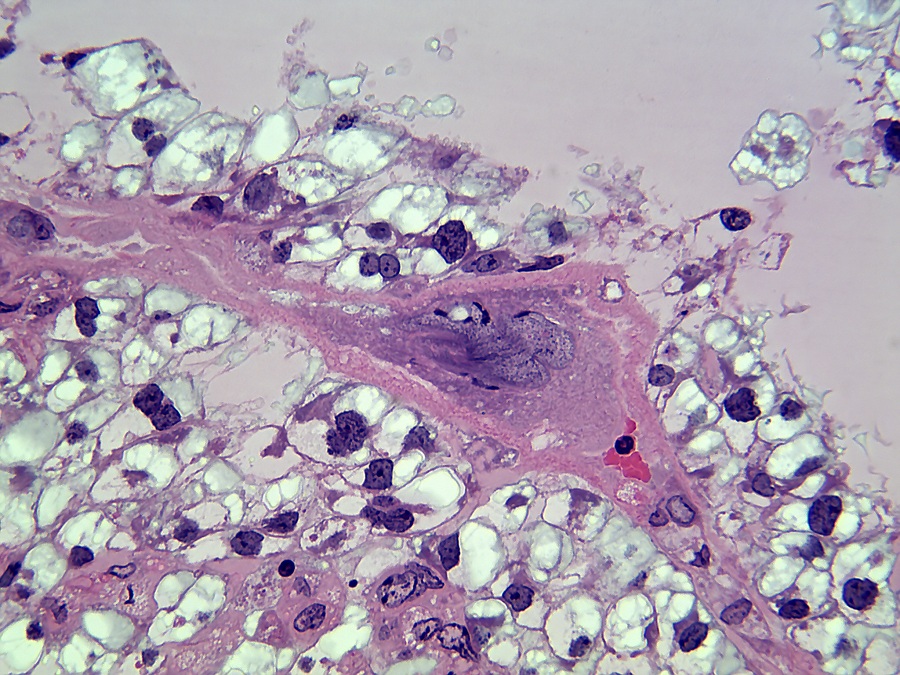

De decidua wordt van de embryonale labyrintische zone gescheiden door de junctionele zone. De junctionele zone bevat maternale bloedvaten (veneuze drainage), trofoblastreuscellen en spongiotrofoblastcellen. Trofoblastcellen zijn over het algemeen erg groot met bizar gevormde of meervoudige kernen. Reusceltrofoblasten zijn, zoals hun naam al zegt, erg groot - tot 100 µm in diameter en bevinden zich het dichtst bij de decidua. Spongiotrofoblasten zijn fagocytisch[6] en kunnen gefagocytiseerde erytrocyten bevatten en bevinden zich dichter bij de labyrintische zone. De labyrintische zone bestaat uit nauw tegenover elkaar liggende foetale en maternale bloedkanalen. De foetale bloedkanalen zijn bekleed met dunne endotheelcellen en bevatten grote onrijpe gekerfde rode bloedcellen, terwijl de maternale bloedkanalen bekleed zijn met grote labyrintische trofoblastcellen.

Reusceltrofoblastcellen[3] zijn betrokken bij de modulatie van de maternale vasculatuur van de decidua en ze produceren verschillende placenta-specifieke hormonen die lijken op het hypofysehormoon prolactine[6]. Dit zijn onder andere Pl-1, Pl-2 (placentalactogeen) en proliferine, die uitsluitend door reuscellen worden uitgescheiden. Pl-1 en Pl-2 moduleren de activiteit van de eierstokken door de productie van luteaal progesteron te stimuleren, wat essentieel is voor het behoud van de zwangerschap. Bovendien zijn Pl-1 en Pl-2 betrokken bij de controle van de borstklierontwikkeling.